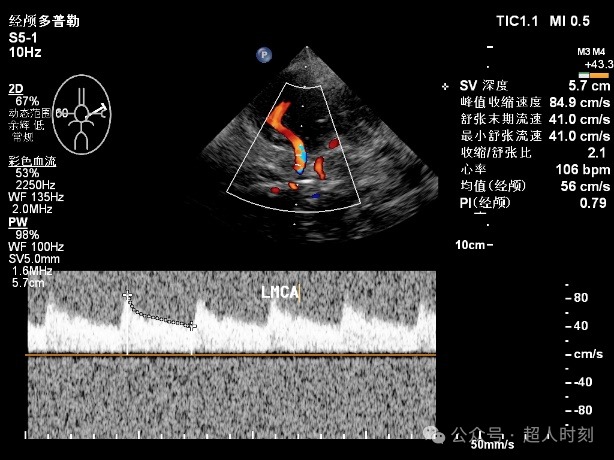

患者,男性,78岁,因“反复头痛头晕‚伴右眼黑朦1+年,肢体麻木偶感上肢无力6+月”入院。颈动脉彩超:右颈内动脉明显狭窄(狭窄率70%-99%),双侧颈总动脉多处狭窄(狭窄率<50%)。TCCD:颅内多支动脉狭窄(见图5)。

图5e 左大脑中动脉狭窄频谱(VP:178cm/s)